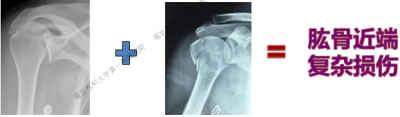

南京医科大学第一附属医院李翔教授通过分享六个临床病例,通过将专业学术内容贯穿融合在临床病例中,来全面剖析肱骨近端复杂损伤——骨折合并肩关节后脱位。

病例1

男性,40岁,摔伤后右肩关节肿痛、活动受限2天。

病例2

男性,48岁,坠落伤致左肩关节肿痛、活动受限1天。

病例1与病例2是同一类损伤吗?

复杂型肩关节骨折后脱位

一、概述

(一)损伤特征:

肩关节后脱位、肱骨头骨折(29%)、肱骨近端骨折(解剖颈18.5%,小结节14.3%,大结节7.8%)。